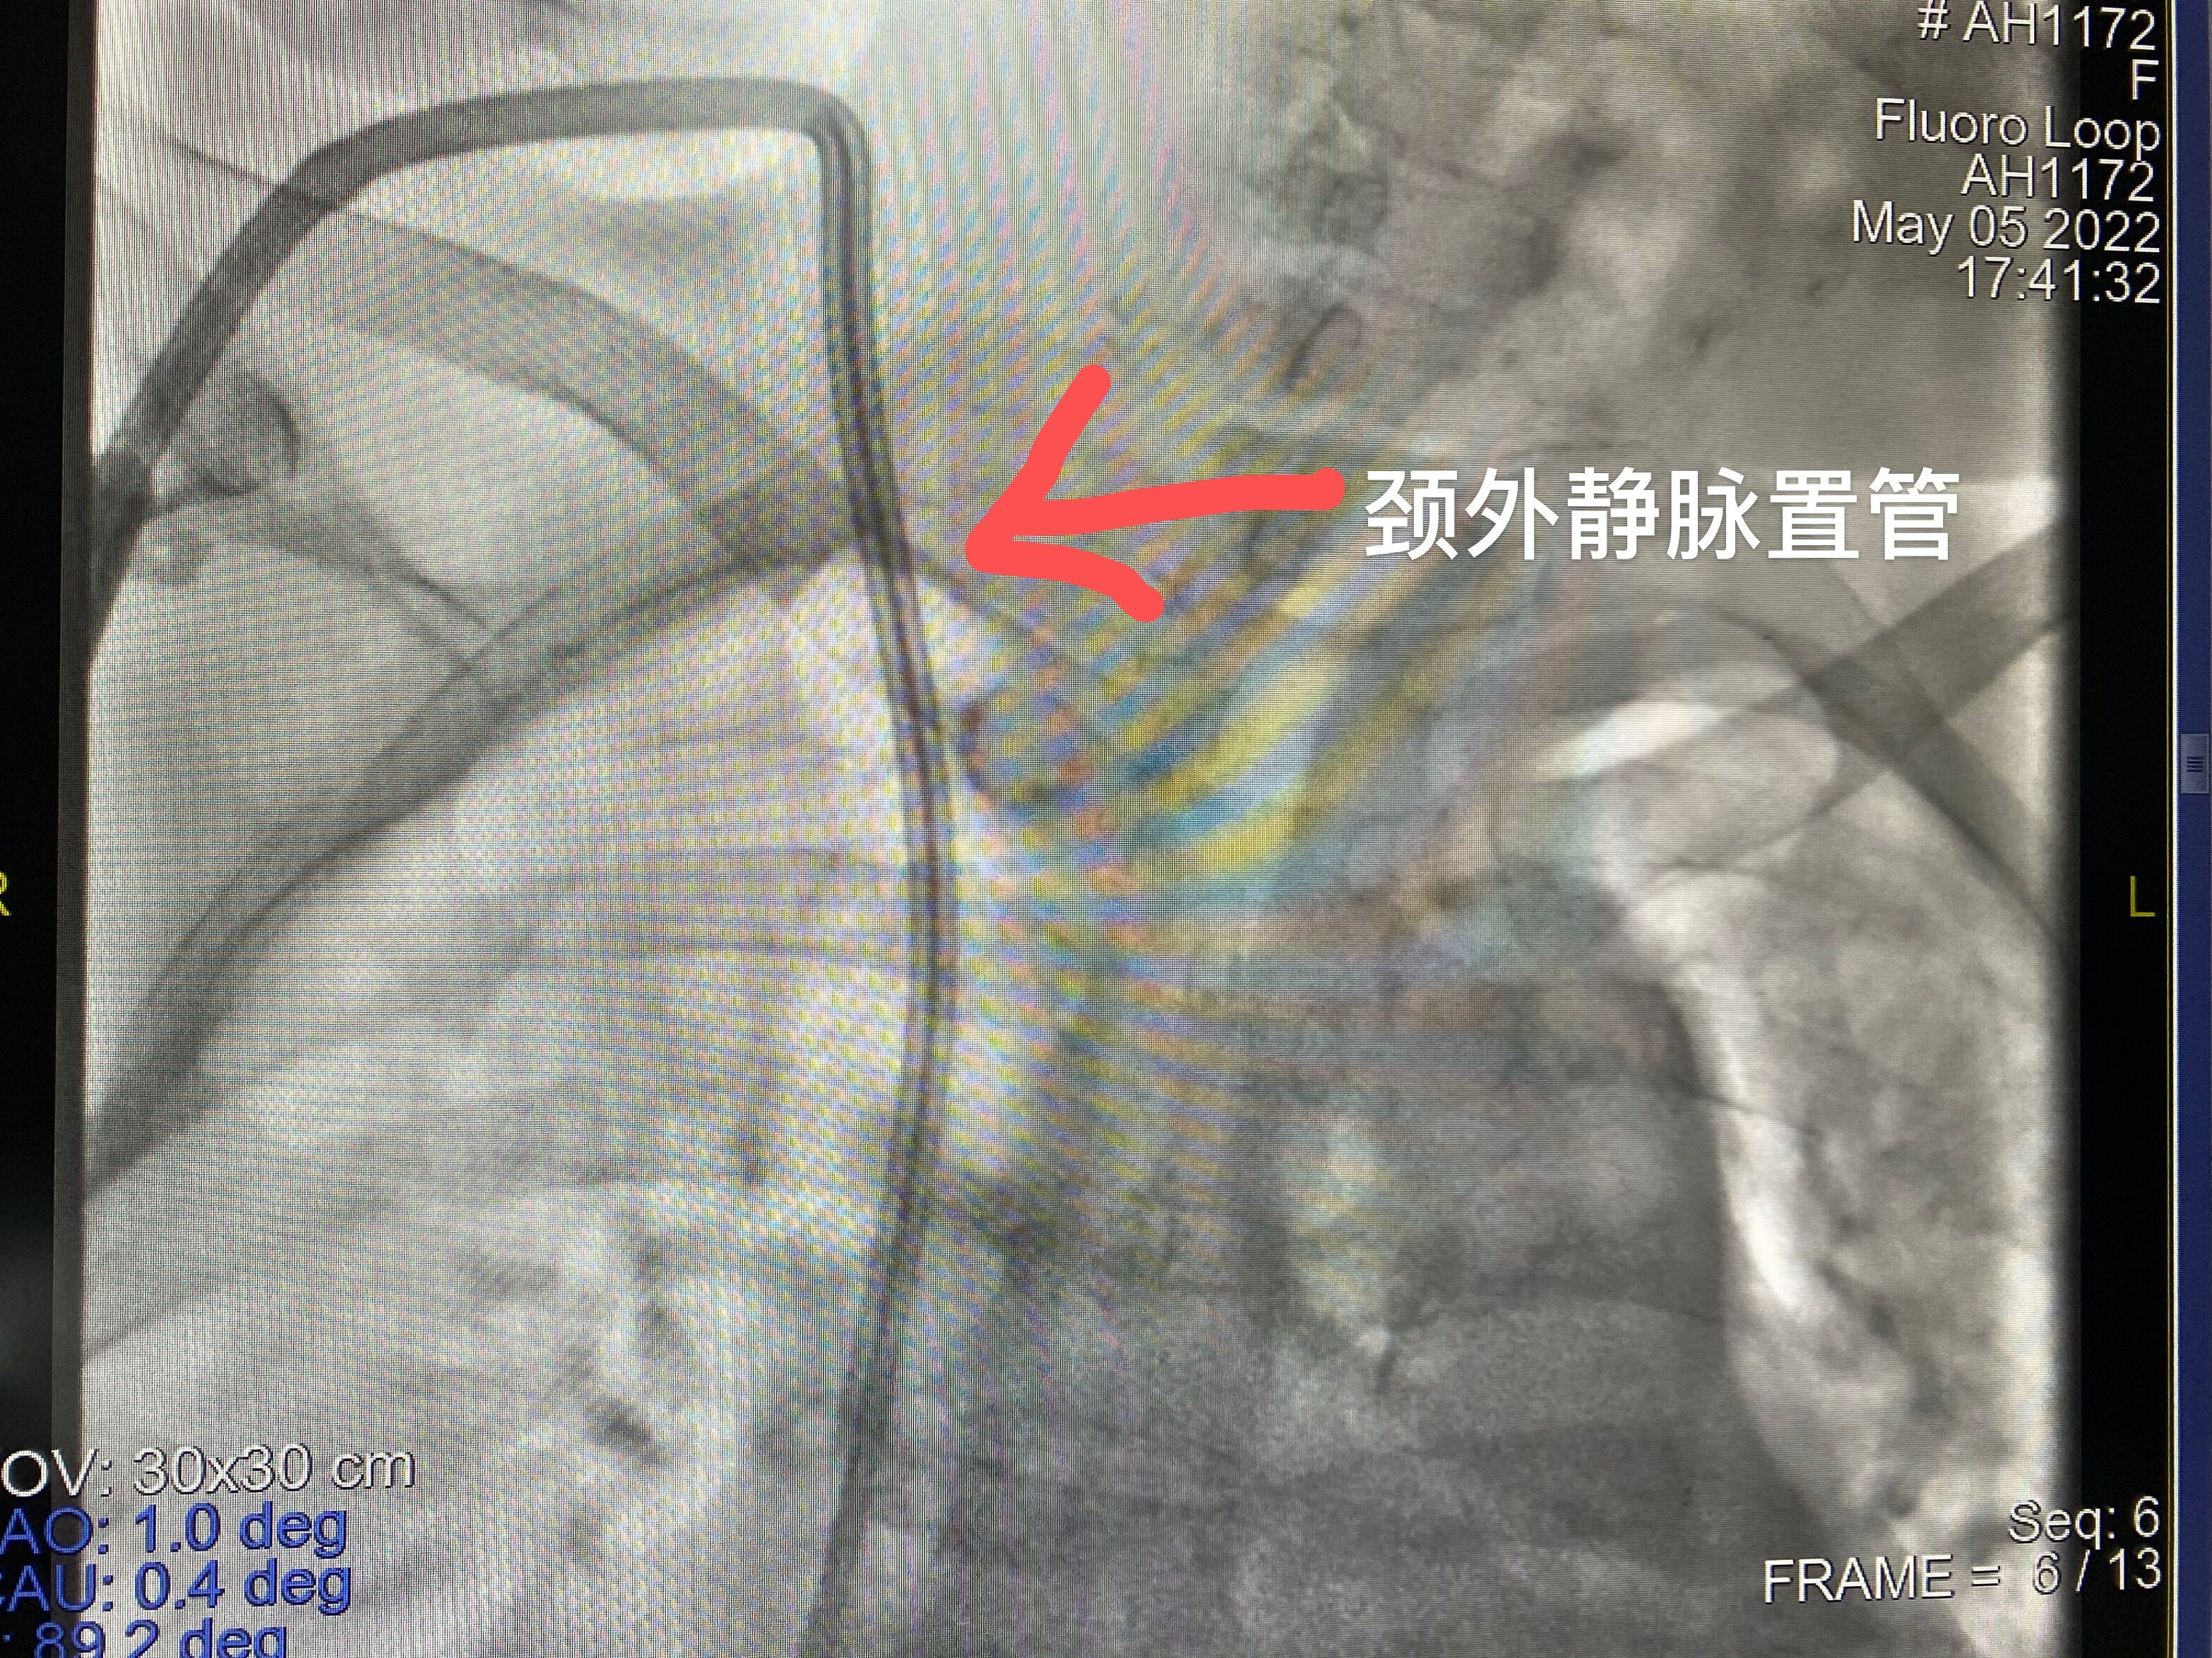

鑒于鄭阿姨目前雙上肢都建立過內(nèi)瘺失敗,右頸內(nèi)靜脈已閉塞,左頸內(nèi)靜脈較細(xì),而鄭阿姨表示不想做瘺了,想安個(gè)導(dǎo)管回去透析等諸多因素,腎內(nèi)科主任胡波經(jīng)過彩超及造影評(píng)估,發(fā)現(xiàn)鄭阿姨右側(cè)頸外靜脈情況還算好,于是胡主任打破常規(guī),另辟蹊徑為其進(jìn)行了右頸外靜脈穿刺置管手術(shù),建立了帶滌綸套的長(zhǎng)期導(dǎo)管。術(shù)后,鄭阿姨的血流量達(dá)到250mL/min,她對(duì)新通路非常滿意,出院后高興地回當(dāng)?shù)蒯t(yī)院繼續(xù)透析了。

頸外靜脈穿刺置管雖然不是最常用的置管部位,但對(duì)于反復(fù)中心靜脈穿刺置管,頸內(nèi)靜脈狹窄或閉塞的患者提供了另一條血管通路途徑。而下肢動(dòng)靜脈內(nèi)瘺的開展對(duì)于上肢血管條件不佳、存在中心靜脈狹窄或閉塞的長(zhǎng)期透析患者開辟了另一條新的透析生命線,解決了血管耗竭透析患者的一大難題。攀鋼總醫(yī)院不斷提高的血透通路技術(shù)為攀西地區(qū)廣大血液透析患者帶來了更大的福音。